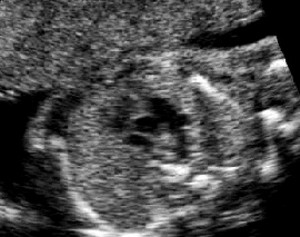

Coartación de aorta

En este otro corte de 3 vasos existe en la imagen y en el vídeo de tres vasos coartación, una gran desproporción en los tamaños relativos entre la arteria pulmonar y la aorta, siendo ésta de mucho menor tamaño que la primera. Este hallazgo es altamente sugestivo de coartación de aorta, y muchas veces es el único dato ecocardiográfico que nos permite sospechar esta cardiopatía.

Tres Vasos. Coartación |